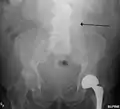

The faint outline of the calcified wall of an AAA as seen on plain X-ray